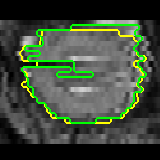

Data augmentation has been widely used for training deep learning systems for medical image segmentation and plays an important role in obtaining robust and transformation-invariant predictions. However, it has seldom been used at test time for segmentation and not been formulated in a consistent mathematical framework. In this paper, we first propose a theoretical formulation of test-time augmentation for deep learning in image recognition, where the prediction is obtained through estimating its expectation by Monte Carlo simulation with prior distributions of parameters in an image acquisition model that involves image transformations and noise. We then propose a novel uncertainty estimation method based on the formulated test-time augmentation. Experiments with segmentation of fetal brains and brain tumors from 2D and 3D Magnetic Resonance Images (MRI) showed that 1) our test-time augmentation outperforms a single-prediction baseline and dropout-based multiple predictions, and 2) it provides a better uncertainty estimation than calculating the model-based uncertainty alone and helps to reduce overconfident incorrect predictions.